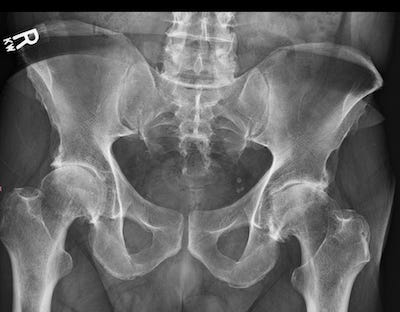

The doctor didn’t need long. One look at the X-ray and he was amazed I could walk… let alone do any of the stupid things I’d been doing. I wasn’t just out of oil. The bearings were gone, the races were chewed, and the whole assembly was grinding itself to death. Or for you tech types: classic bone-on-bone contact, a femoral head that wasn’t even round anymore, and it was grinding straight into the acetabulum.